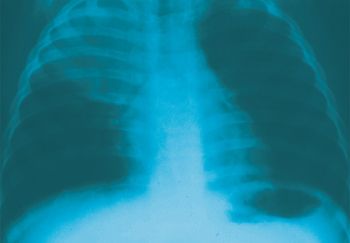

Images of allergic fungal rhinosinusitis, Wegener granulomatosis, interstitial lung disease, and other respiratory disorders show up in this photo essay.